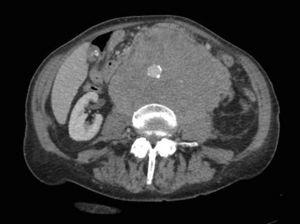

A computed tomography scan showed a heterogeneous retroperitoneal mass measuring 14×11cm surrounding the abdominal aorta and the renal vessels, without invading them (Figs. 1 and 2).

Fig. 2